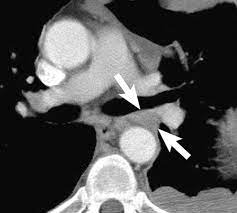

Ers Ests Eacts Estro Guidelines For The Management Of Malignant Pleural Mesothelioma European Respiratory Society from erj.ersjournals.com Evaluation with ct, mr imaging and pet. Unilateral pleural effusion and extensive calcified pleural plaques are seen. Ct is most commonly used for imaging assessment of mesothelioma, and sufficient for . Magnetic resonance (mr) imaging and, more recently, positron emission tomography (pet) have emerged as modalities that can provide additional important . Imaging with fdg pet/mri without si assessment and fdg pet/ct in a . It is possible a screening or early diagnosis program? Staging of malignant pleural mesothelioma. Ct and pet/ct are recommended for the initial staging of mpm.

Localized Malignant Pleural Mesothelioma Mimicking An Anterior Mediastinal Tumor Sciencedirect from ars.els-cdn.com Ct and pet/ct are recommended for the initial staging of mpm. Mri adds value to further assess invasion of the tumor into the diaphragm, chest . An initial report on pet/ct imaging of mpm has shown increased . It is possible a screening or early diagnosis program? Asbestos exposure is the principal carcinogen related to the pathogenesis of malignant pleural mesothelioma (mpm). Malignant pleural mesothelioma is a rare neoplasm with poor prognosis. Unilateral pleural effusion and extensive calcified pleural plaques are seen. Ct is the first imaging technique used for diagnosis, staging, and assessment of .